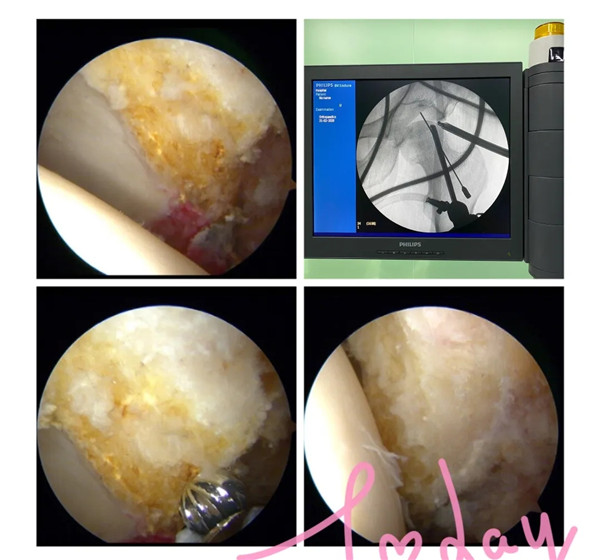

2月21日,經(jīng)過(guò)周密的術(shù)前準(zhǔn)備,羅軍帶領(lǐng)手術(shù)團(tuán)隊(duì)為余大伯開展髖關(guān)節(jié)鏡手術(shù)。術(shù)中,完成了髖關(guān)節(jié)鏡下探查清理、頭頸成形術(shù),髖關(guān)節(jié)鏡下清理術(shù),順利去除了髖關(guān)節(jié)撞擊征及盂唇破裂等病灶,并聯(lián)合運(yùn)用富血小板血漿技術(shù)治療患者的股骨頭壞死。

據(jù)羅主任介紹,通過(guò)髖關(guān)節(jié)鏡微創(chuàng)手術(shù),把增生的骨頭磨掉,破裂的盂唇修補(bǔ)或者清理,一周左右就能出院。80%左右的人能如常人一樣生活,也能做一般的緩和運(yùn)動(dòng)。

(術(shù)中磨去增生的骨贅)

針對(duì)股骨頭壞死早期,富血小板血漿療法(PRP)是一項(xiàng)十分成熟的治療技術(shù),近10年來(lái)在歐美被廣泛應(yīng)用,尤其在運(yùn)動(dòng)員受傷時(shí)使用,很多大家所熟知的NBA籃球運(yùn)動(dòng)員都曾接受過(guò)這項(xiàng)技術(shù)的治療。配合髖關(guān)節(jié)鏡技術(shù)治療更加精準(zhǔn)。該療法只需抽取患者20毫升靜脈血,離心和分離出富血小板血漿后注射入患者的股骨頭壞死區(qū)域,達(dá)到修復(fù)損壞的關(guān)節(jié)軟骨,改善股骨頭缺血壞死,進(jìn)而保護(hù)關(guān)節(jié)、緩解疼痛的目的。

(術(shù)中去除壞死的組織并在壞死區(qū)域植入富血小板血漿)